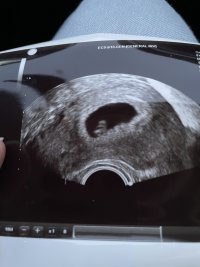

Jeg måtte gå å tisse fordi blæren var for full til å se ordentligHvordan er dette med blære og innvendig ul? Burde man ha full blære eller?![]()

Hadde tisset 1,5-2 timer før timen og var ikke tissetrengt.Er henvist og håper veldig på ledig tid idag (de antydet at det kanskje ble) så tenkte jeg skulle være så forberedt som muligVi var på privat TUL nå i uke 8, men man får to offentlige UL, en mellom uke 11-13, og en mellom uke 19-21![]()